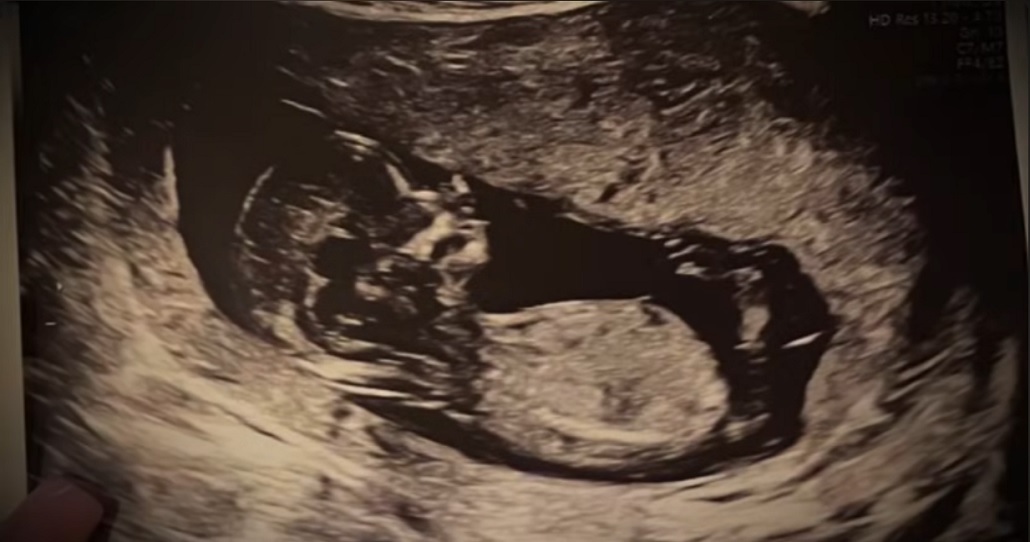

The family was brimming with anticipation for the future,twenty year old Saga was 31 weeks , or seven months , pregnant with her partner Mohammedamid Ibraheim, whom they affectionately called Amin.

The young couple had been together since the fall of 2021, and they were expecting a healthy baby boy.

Saga was eager t become a mother, frequently sharing her pregnancy photos with friends and family.

Her close knit family were highly supportive of her journey into motherhood Saga had been diligently preparing for he baby’s arrival and rolling in prenatal classes and gathering essential baby gear.